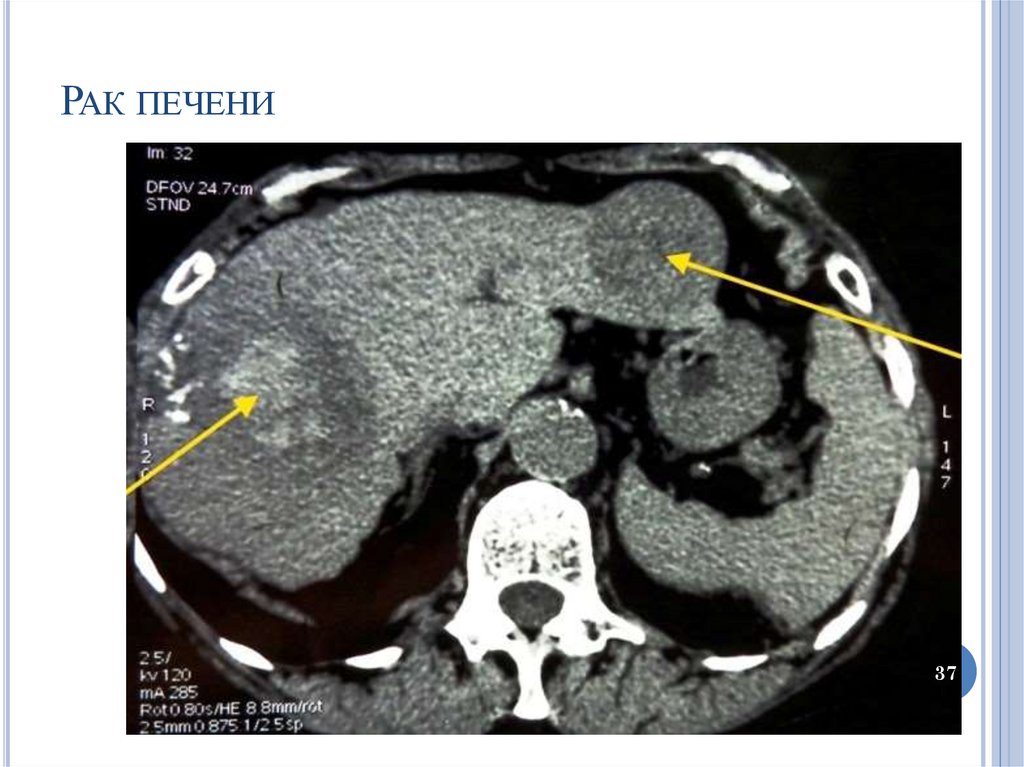

37.

РАК ПЕЧЕНИ

37